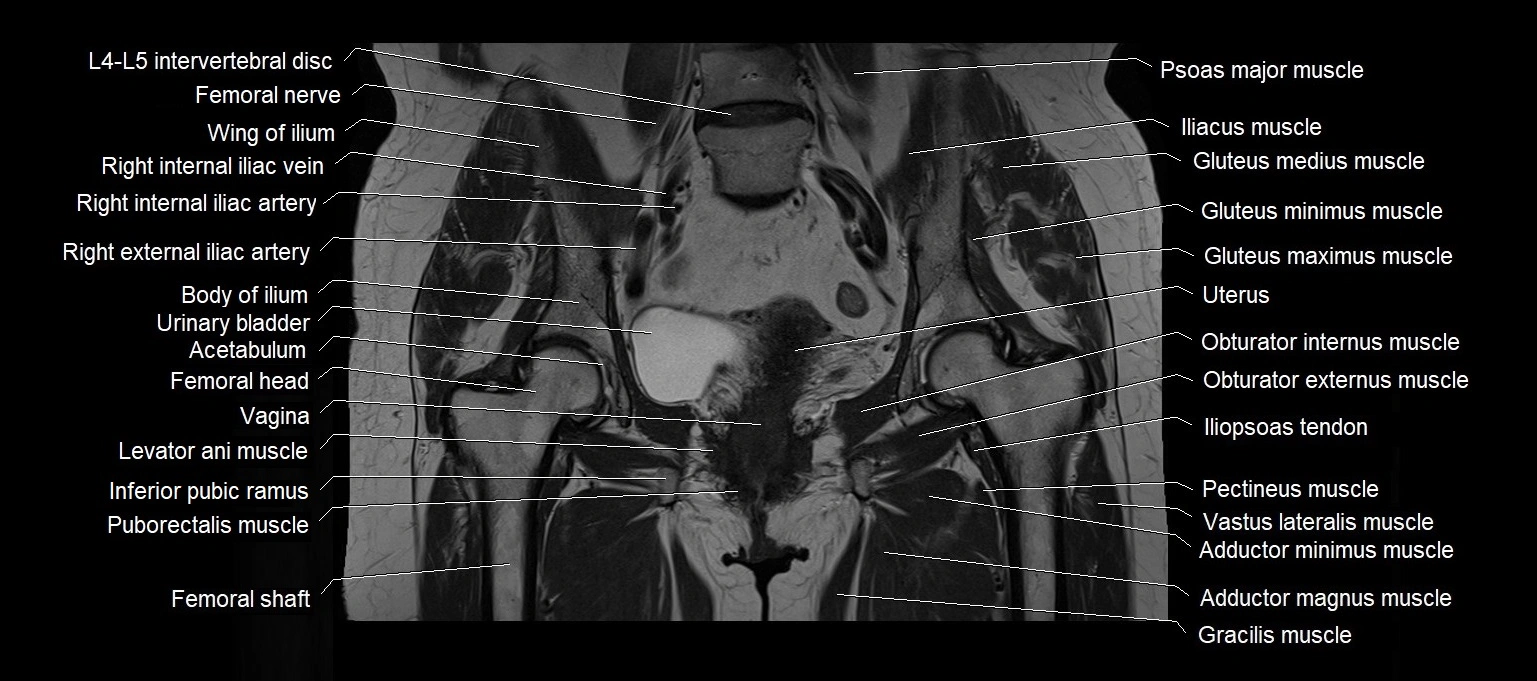

MRI images